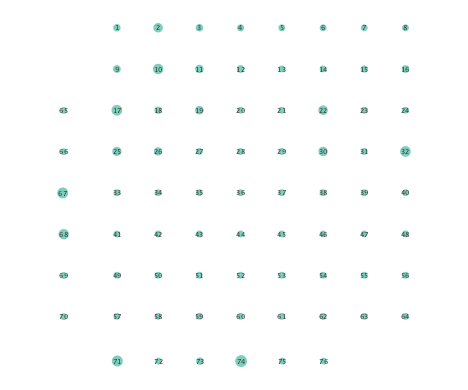

Finally, Figure 6 depicts the closeness centrality computed per node in the inferred networks. Closeness centrality measures how reachable a node is from all other nodes, and is generally defined as the reciprocal of the sum of geodesic distances of the node from all other nodes in the network; see also [24]. Once again, Figure 6 depicts a more general decrease in closeness centralities after seizure onset in networks inferred by the nonlinear SVARM, as compared to the linear variant. This empirical result indicates a change in reachability between regions of the brain during an epileptic seizure.

Moreover, the performance of K-SVARM with data-driven kernel selection was also tested. Figure 7 illustrates the per node degree as well as the closeness centrality of networks inferred from preictal and ictal phases. Consistent with Figures 3 and 6, Figure 7 again reveals universal decrease in node degrees as well as closeness centrality at seizure onset.